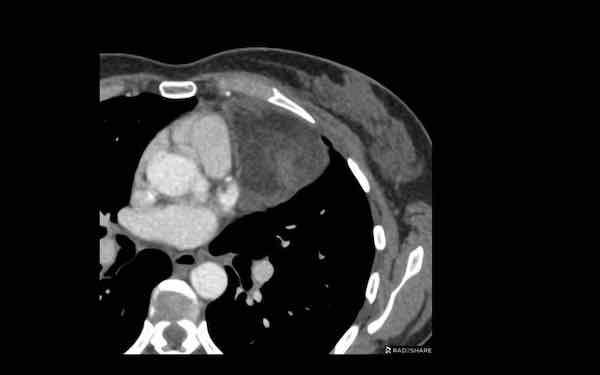

Các hình ảnh này của một bệnh nhân nam 68 tuổi, vừa trải qua phẫu thuật bắc cầu động mạch vành.

Bệnh nhân than phiền khó thở.

Nồng độ D-dimer cao và CT được thực hiện để tìm kiếm thuyên tắc phổi.

Hình ảnh

Có một khối trong trung thất trước mạch máu.

Tỷ trọng là 44